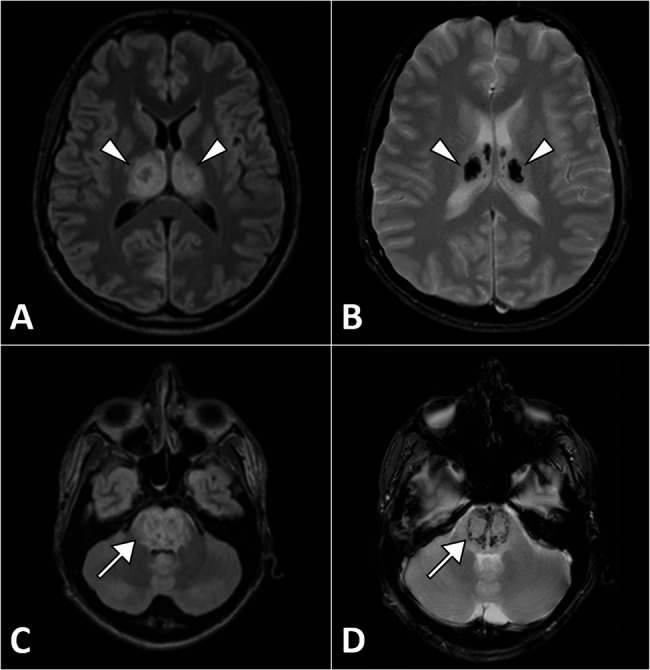

Case presentation: A 19-year-old previously healthy male presented with a two-day history of fever, headache, altered mental status, and seizures. On admission, he was febrile, with impaired consciousness. Initial investigations showed leukocytosis, elevated C-reactive protein, and cerebrospinal fluid analysis indicative of inflammation without bacterial or fungal pathogens. Brain MRI revealed bilateral symmetrical lesions in the thalami, putamen, and brainstem, consistent with acute necrotizing encephalopathy. Polymerase chain reaction testing of cerebrospinal fluid and nasopharyngeal swabs confirmed adenovirus as the causative agent. The patient was managed with seizure control, corticosteroids for cerebral edema, and supportive care, including mechanical ventilation and physiotherapy. Follow-up imaging demonstrated regression of thalamic and pontine lesions. The patient showed partial neurological recovery but required transfer to a long-term care facility for rehabilitation, with persistent functional disability.